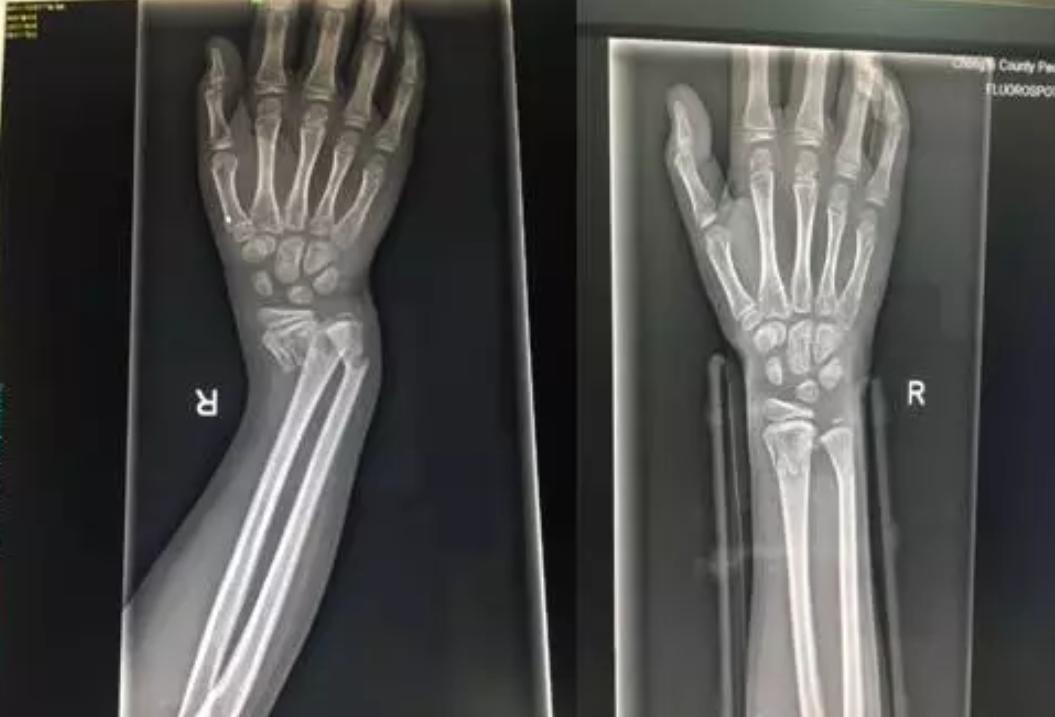

由上图可以看出孩子的右手腕明显的畸形

DR片提示右桡尺骨远端骨折。因为骨折严重错位,孩子疼痛的已经脸色惨白,我们将治疗方式提供给患儿家属,征得同意后实施正骨手法复位。准备好一切所需要的物品,如绷带、夹板、扎带、棉垫、压垫。孩子很坚强,积极配合,吴医生与朱医生默契配合,在场的人都屏住呼吸,希望医生可以一次复位成功,避免孩子再承受更多的痛苦。牵引、复位一气呵成。

在场的人都松了一口气,固定夹板,交待关注事项,复查。让我们看看复查前、后的DR片吧!